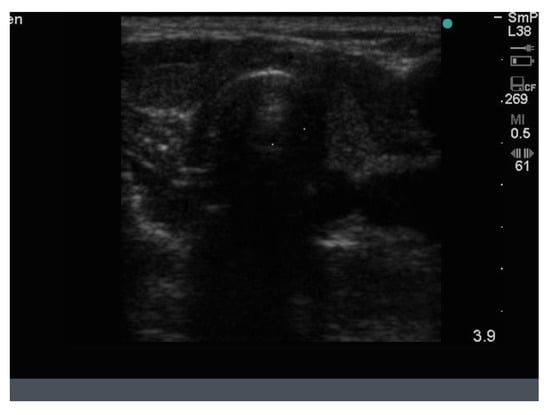

Thirdly, an example of a much smaller lesion that turned out to be papillary cancer is shown in Figure 13. The nodule is only 10–12 mm in size, hypoechoic and has an unusual and irregular edge. Three years earlier the same lesion was seen on ultrasound, and its size then was 8 × 9 mm with no other suspicious features and no microcalcifications nor feeding vessels or blood vessels, indicating that it had grown very little over the intervening 3 years. It was considered suspicious on ultrasound because of its shape and edge. The lesion was shown to be suspicious for papillary cancer at FNAB and confirmed at hemi thyroidectomy.

Figure 13.

Small 10 mm nodule with an overall blurry irregular edge (arrow) that is taller than wide and hypoechoic, shown from FNAB to be papillary cancer.